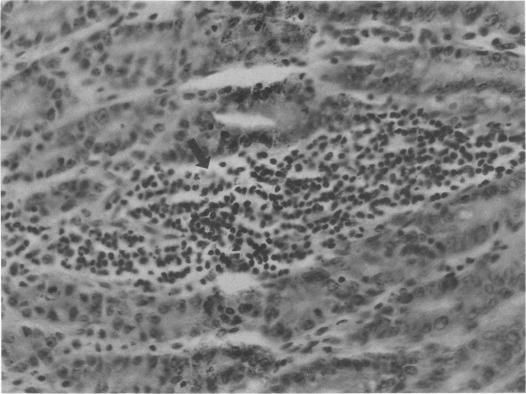

Listeria monocytogenes colonized the gastrointestinal tract of adult germfree rats (10(10) to 10(11)/g, dry weight) within 24 h after oral exposure. Between 3 and 14 days after monoassociation, L. monocytogenes caused a self-limiting pseudomembranous colitis, bacteremia, and infection of the spleen and liver. Monoassociation of rats with Listeria for 8 weeks stimulated 32- and 4-fold increases in serum immunoglobulin A (IgA) and IgG, respectively, whereas serum IgM decreased 2-fold. The normal microbial flora was inhibitory to Listeria colonization, since L. monocytogenes was cleared from the gastrointestinal tract of formerly monoassociated rats within 20 days after conventionalization and did not colonize the gastrointestinal tract of conventional rats after intragastric instillation of 10(8) viable L. monocytogenes. Listeria-monoassociated rats delivered large litters of healthy pups whose gastrointestinal tracts were slowly colonized with L. monocytogenes. between 3 and 60 days of age, Listeria-monoassociated rat pups exhibited eight- and fourfold increases in serum IgG and IgM, respectively; however, serum IgA was elevated (16-fold) only at 9 to 15 days of age. Adult Listeria-monoassociated rats had acquired cellular resistance to intravenous challenge with L. monocytogenes. Prolonged monoassociation of L. monocytogenes in rats attenuated its virulence for conventional rats.